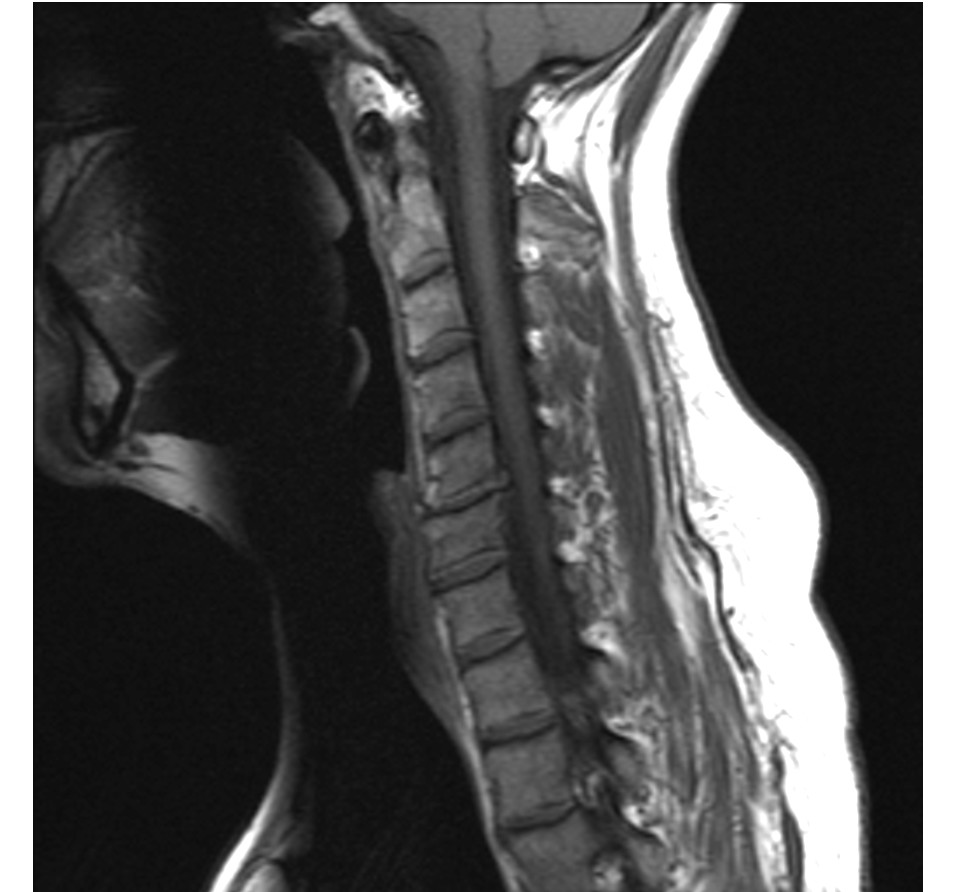

Смирнов описывает реальный случай из своей практики: пациент с грыжами размером 1,5 сантиметра. По признанию автора, на первых сеансах добиться быстрого результата было сложно — тело находилось в состоянии сильной декомпенсации. Однако после того, как удалось устранить перегрузку по всей системе, нормализовать активность пациента и добавить корректную дозированную нагрузку, через 8 месяцев контрольное МРТ показало: грыжи существенно уменьшились.

Механизм «высыхания» объясняется просто. Выпавшая грыжа — это мешочек с содержимым пульпозного ядра. Когда остеопат устраняет механическое давление на сегмент, воспаление стихает, отёк уходит. Организм «понимает», что нестабильности больше нет, и начинает дегидратировать выпавший участок — тот медленно усыхает и превращается в тонкую пленку, не давящую ни на какой нерв. На контрольных снимках МРТ врачи сообщают пациенту, что грыжи «исчезли».

Смирнов предупреждает: никакой остеопат не «вправляет» грыжу механически — это анатомически невозможно. Снимки документируют именно физиологическое высыхание, для которого остеопат лишь создал благоприятные условия. Именно поэтому автор рекомендует делать контрольное МРТ не раньше чем через год после начала лечения: дегидратация — это глубокий физиологический процесс, занимающий месяцы.

По словам Смирнова, выпавшая грыжа способна дегидратироваться и превратиться в тонкую плёнку, которая не давит на нервы — это подтверждается контрольными снимками МРТ. Механизм естественный: когда остеопат устраняет перегрузку сегмента, организм перестаёт нуждаться в грыже как «прокладке» и постепенно её высушивает. Процесс занимает от 6 до 12 месяцев. Контрольное МРТ автор рекомендует делать не раньше чем через год.